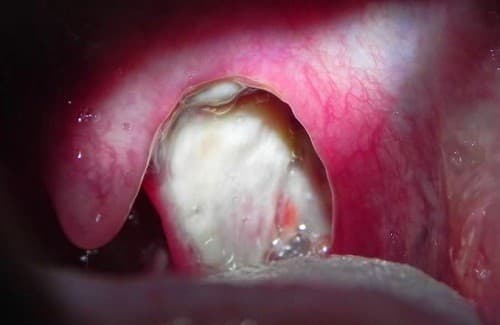

Viêm amidan hốc mủ Chất bã đậu tiết ra

Viêm amidan hốc mủ là thể viêm amidan mạn tính. Chất bã đậu tiết ra nhiều hơn bình thường rồi ứ đọng trong các hốc amidan gây ra các chấm trắng trên amidan.

Tuy nhiên với cấu trúc được phân chia thành nhiều hốc, ngăn, vi khuẩn cũng dễ dàng xâm nhập, lâu ngày tạo nên các khối mủ bã đậu và vón cục. Đồng thời với sự cọ xát của thức ăn khi đi qua thành họng, các kén mủ trong hốc amidan bị bật ra. Mủ có hình dạng như hạt tấm, có màu trắng xanh và mùi hôi.

Khi mắc phải viêm amidan hốc mủ, người bệnh thường có các biểu hiện như đau rát họng, có dấu hiệu sốt hoặc người ngai ngái muốn sốt, có đờm trong cổ nhưng rất khó khạc hay nuốt, hơi thở có mùi hôi. Có mủ trong amidan. Khi ho hoặc hắt hơi kèm cùng cái hạt nhỏ lấm tấm màu trắng xanh có mùi hôi khó chịu.